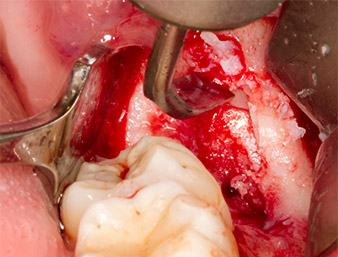

A continuación, se utilizó un inserto para la retirada de los sedimentos periodontales (Piezomed P1) y se amplió mínimamente el surco periodontal del resto radicular (figura 8).

El mismo inserto activado se introdujo en el canal radicular y aflojó el fragmento gracias a sus vibraciones microoscilantes (figuras 9 y 10).

Piezomed P1

Imagen 9: El fabricante recomienda el inserto Piezomed P1 sobre todo para la extracción periodontal de placa, pero también resulta adecuado para propósitos quirúrgicos. En este caso, se colocó en el canal radicular después de una ampliación mínima del surco periodontal.